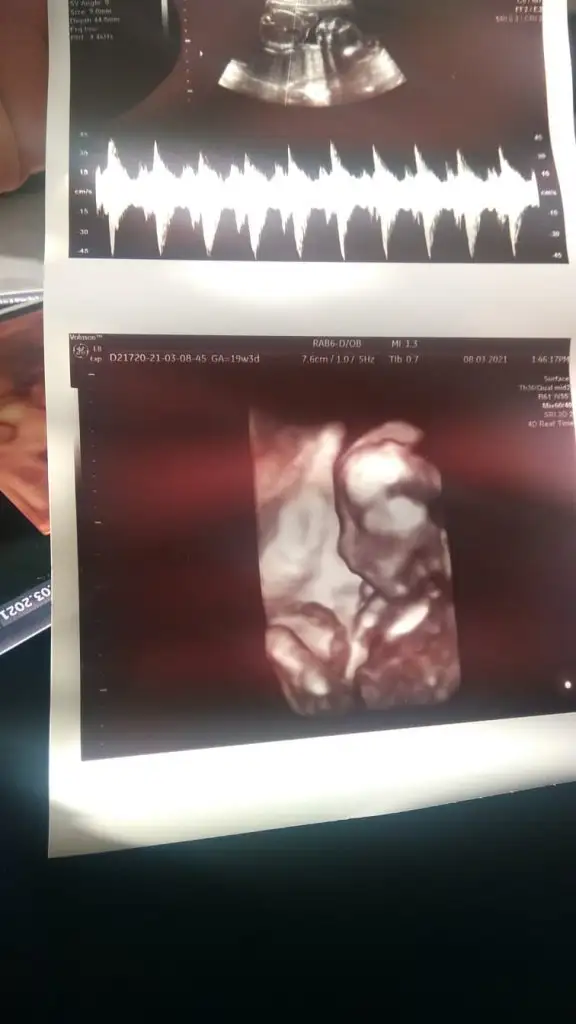

En iyi 11 12 13 haftalar olmalıIkra meyra kardeşimin 19 haftalik doktor söylemedi anlaşılıyor mu cinsiyeti

Teşekkürler erkek demiştiniz o haftalarda bugün gittiler doktora doktor kardeşime söylemedi eltisine söylemiş sürpriz olacak cinsiyet partisi yapacaklarmış cumaEn iyi 11 12 13 haftalar olmalı